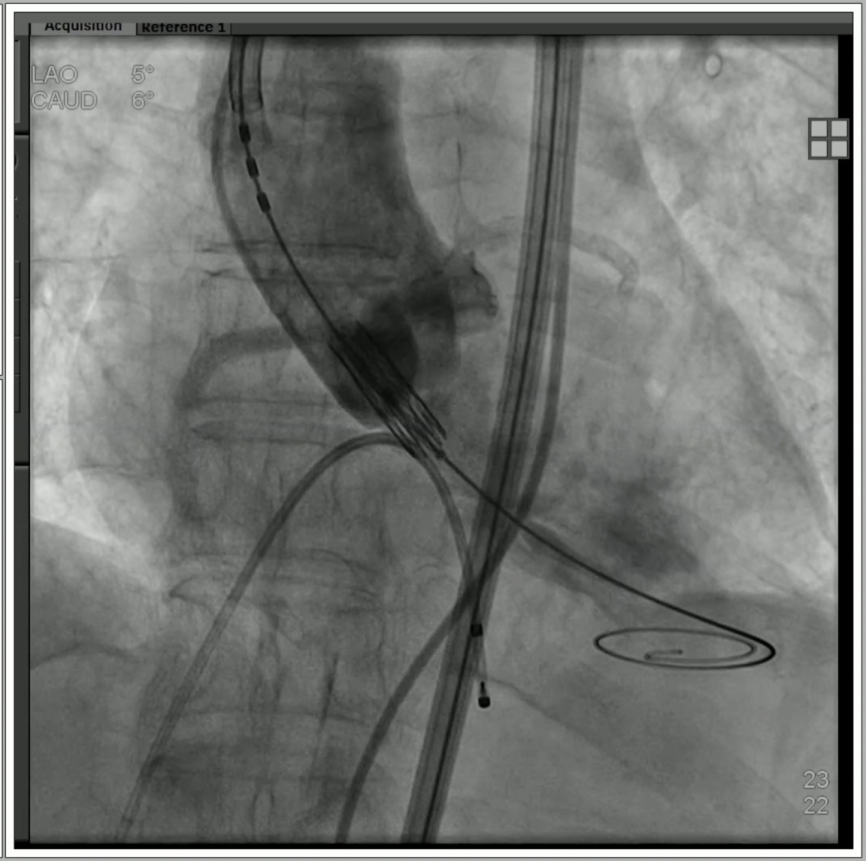

4、通过支撑导丝,送入23mm SAPIEN 3瓣膜,使用独特调弯功能,保证安全过弓并成功跨瓣;

5、调整至共平面角度,瓣膜到位,快速起搏下精准释放瓣膜。